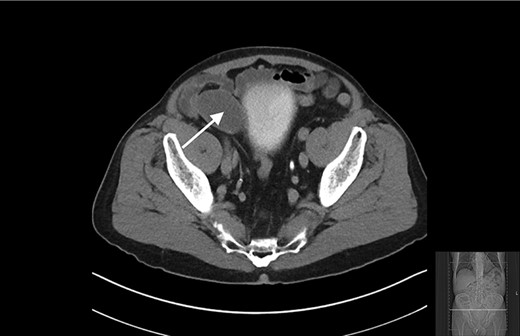

The appendiceal mucocele was visualised during the laparoscopic procedure. The adhesions surrounding the apex of the mucocele were released. There appeared to be volvulus of the appendix (Fig. 3). The main body of the appendix was normal with no evidence of malignancy seen during the surgery. On this basis, a right hemicolectomy was not performed. The appendix was amputated at the base and removed with the base tied (Fig. 4).